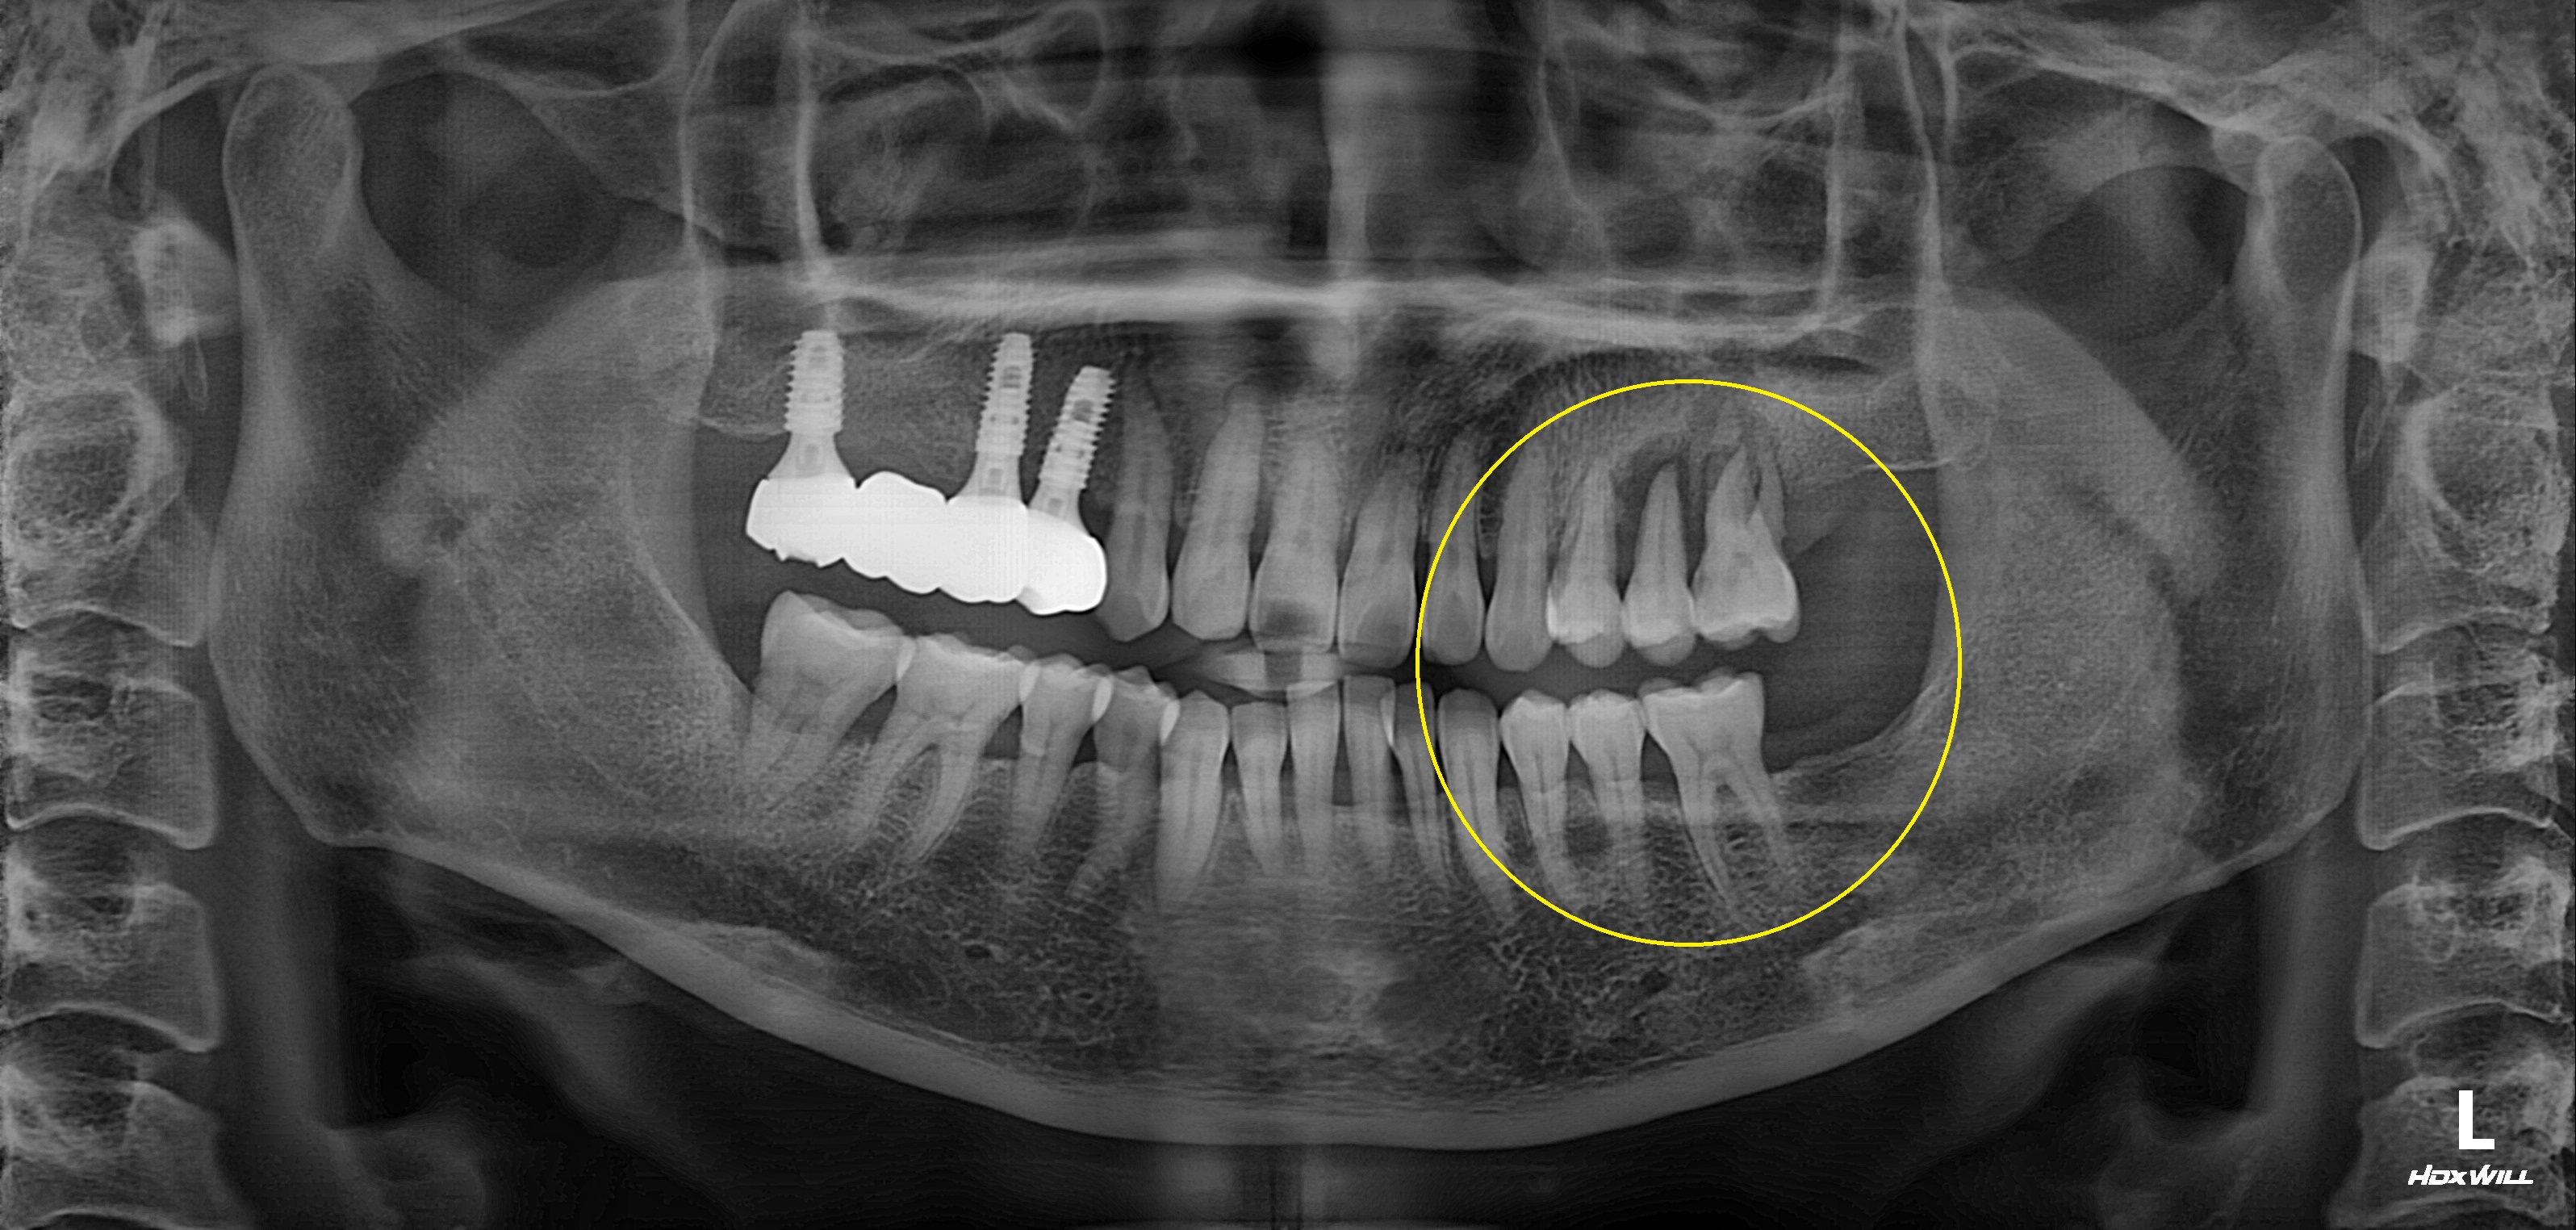

구치부 임플란트 식립사례

전후사진

상악 구치부 임플란트 식립사례